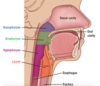

USE IMAGE!!!!